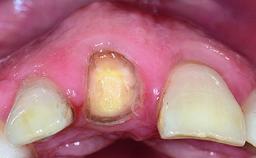

Replacement of a Failing Upper Left Central Incisor: Immediate Placement of an RC Bone Level Implant and Provisionalization

Loading Protocol Immediate

Provisional Implant-Supported Prosthesis Prosthodontic margin < 3 mm apical to mucosal margin Prosthodontic margin < 3 mm apical to mucosal margin